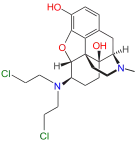

- Chloroxymorphamine [4]

Chloroxymorphamine Chloroxymorphamine |